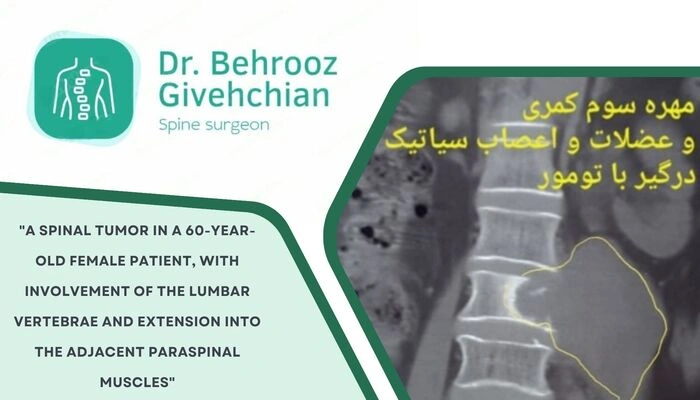

۲. سرطان و متاستاز استخوانی

برخی سرطانها مانند سینه، پروستات، ریه و کلیه تمایل دارند سلولهای سرطانی خود را به استخوانها، به ویژه مهرههای ستون فقرات، منتقل کنند (متاستاز). سلولهای سرطانی با ترشح موادی مانند فاکتورهای محرک استئوکلاستها باعث افزایش تجزیه بافت استخوانی میشوند. این روند، ساختار استخوان را تضعیف کرده و آن را مستعد شکستگی میکند. گاهی اوقات، شکستگی پاتولوژیک مهره اولین علامت یک سرطان پنهان است.

۳. تومورهای خوش خیم یا اولیه استخوان

برخی تومورهای اولیه یا خوش خیم استخوان، مانند میلوم متعدد (Multiple Myeloma)، با تکثیر سلولهای غیر طبیعی در مغز استخوان، محیط استخوان را تخریب میکنند. این سلولها پروتئینهایی تولید میکنند که فعالیت استئوکلاستها را افزایش و فرآیند معدنی شدن استخوان را مختل میکند، در نتیجه مهرهها نازک و شکننده میشوند.